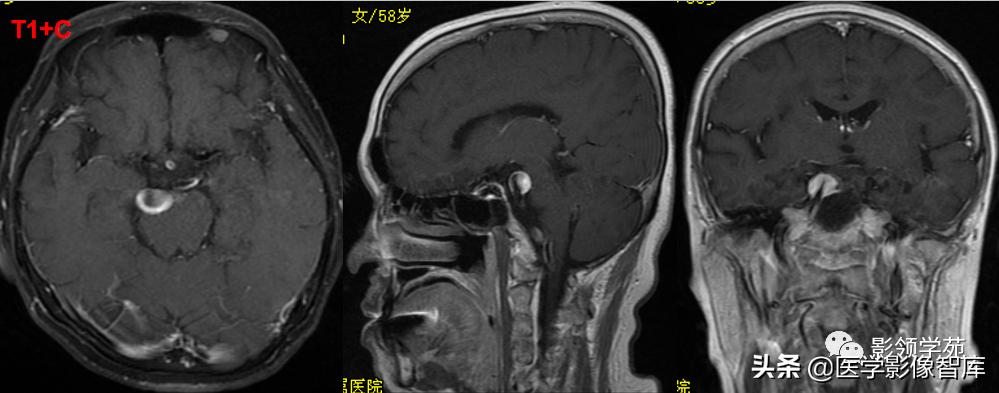

女 72岁,发现糖尿病3年余

鞍上区见一团块状稍高密度影,边界尚清,密度均匀。

鞍上右上方见一类椭圆形流空影。

病灶明显强化(瘤内血栓未强化),边界清楚,与右侧颈内动脉海绵段分界不清。垂体大小、形态未见异常。